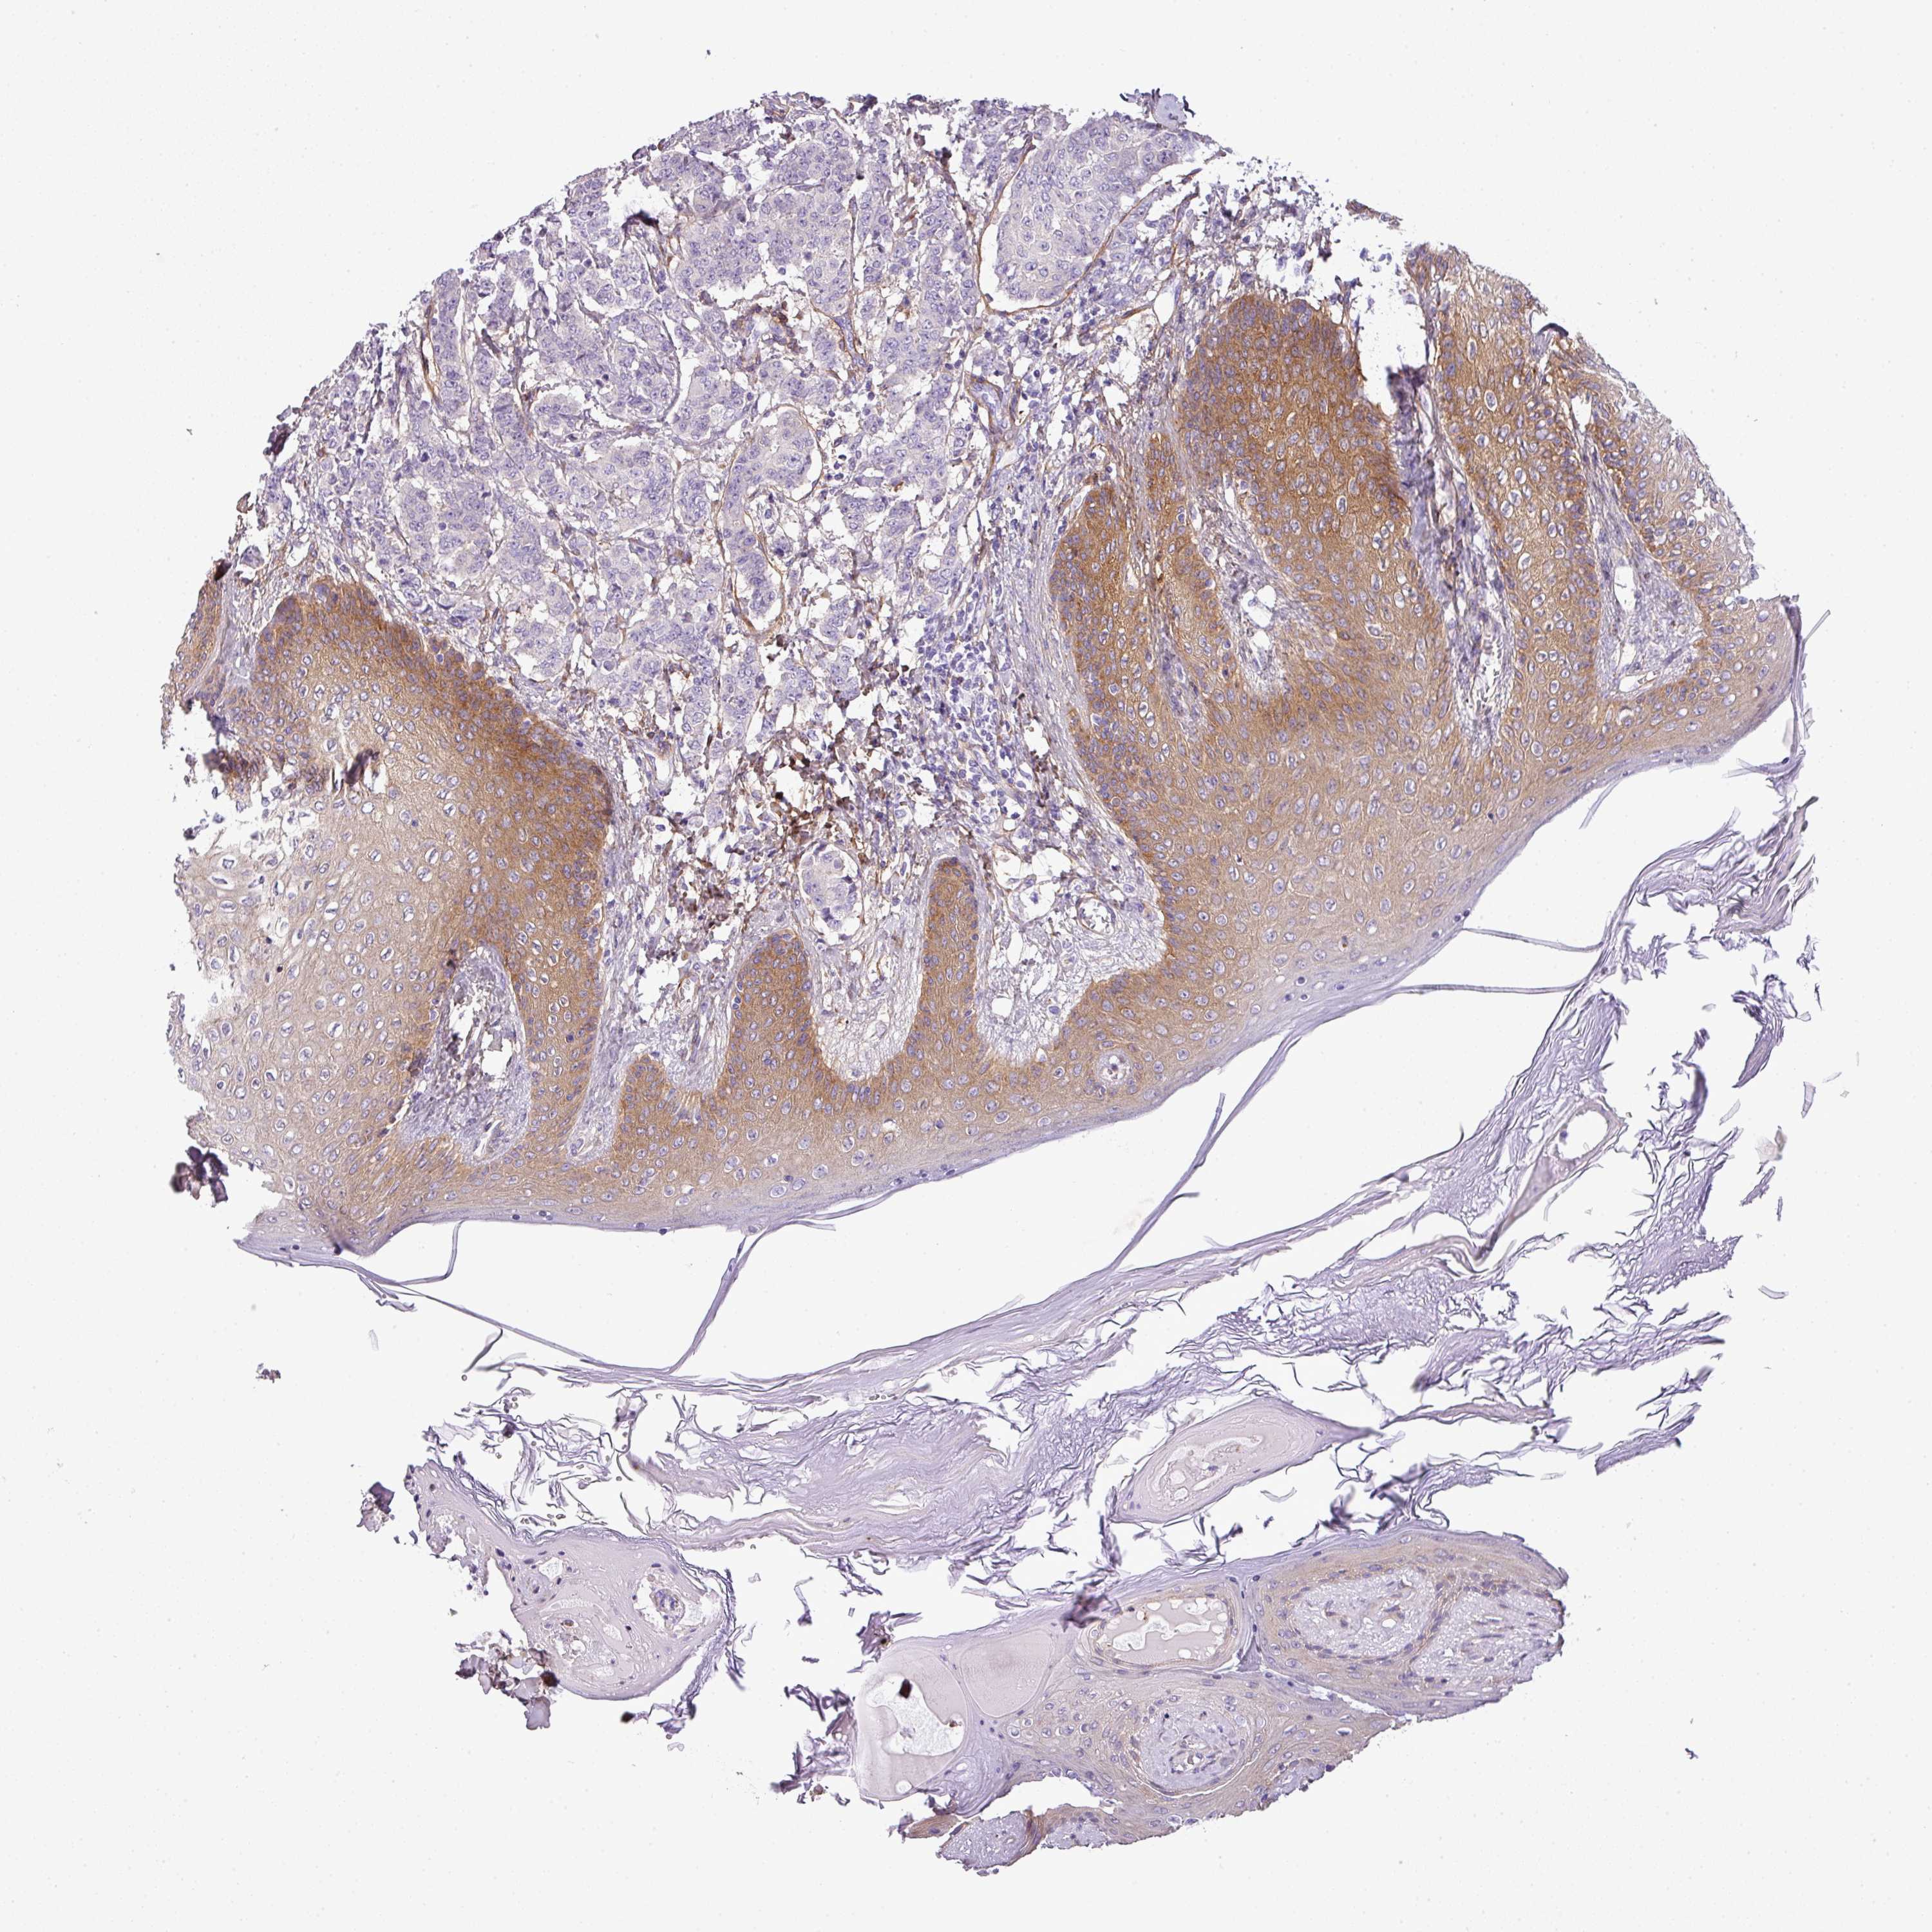

BRCA TCGA BRCA VALIDATION PROTEIN EXPRESSION

ANTIBODIES

AND

VALIDATION